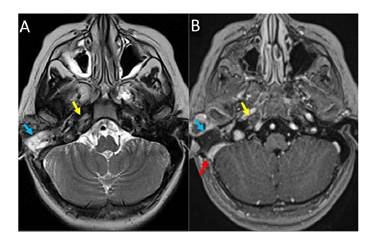

En la resonancia magnética cerebral con contraste realizada nueve días después del procedimiento quirúrgico, se evidenció regresión de los signos inflamatorios en las celdillas mastoideas y el ápex petroso, y recanalización de la trombosis en los senos venosos y la yugular interna (figura 4). Además, hubo resolución de los síntomas de hipertensión intracraneal. Sin embargo, a los dos meses del ingreso hospitalario la parálisis del VI nervio craneal persistía.